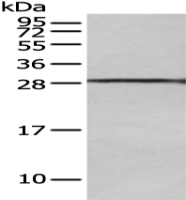

Description Anti-MTBP rabbit polyclonal antibody

Applications ELISA, IHC

Immunogen Synthetic peptide of human MTBP

Reactivity Human, Mouse

Content 0.5 mg/ml

Host species Rabbit

Ig class Immunogen-specific rabbit IgG

Purification Antigen affinity purification